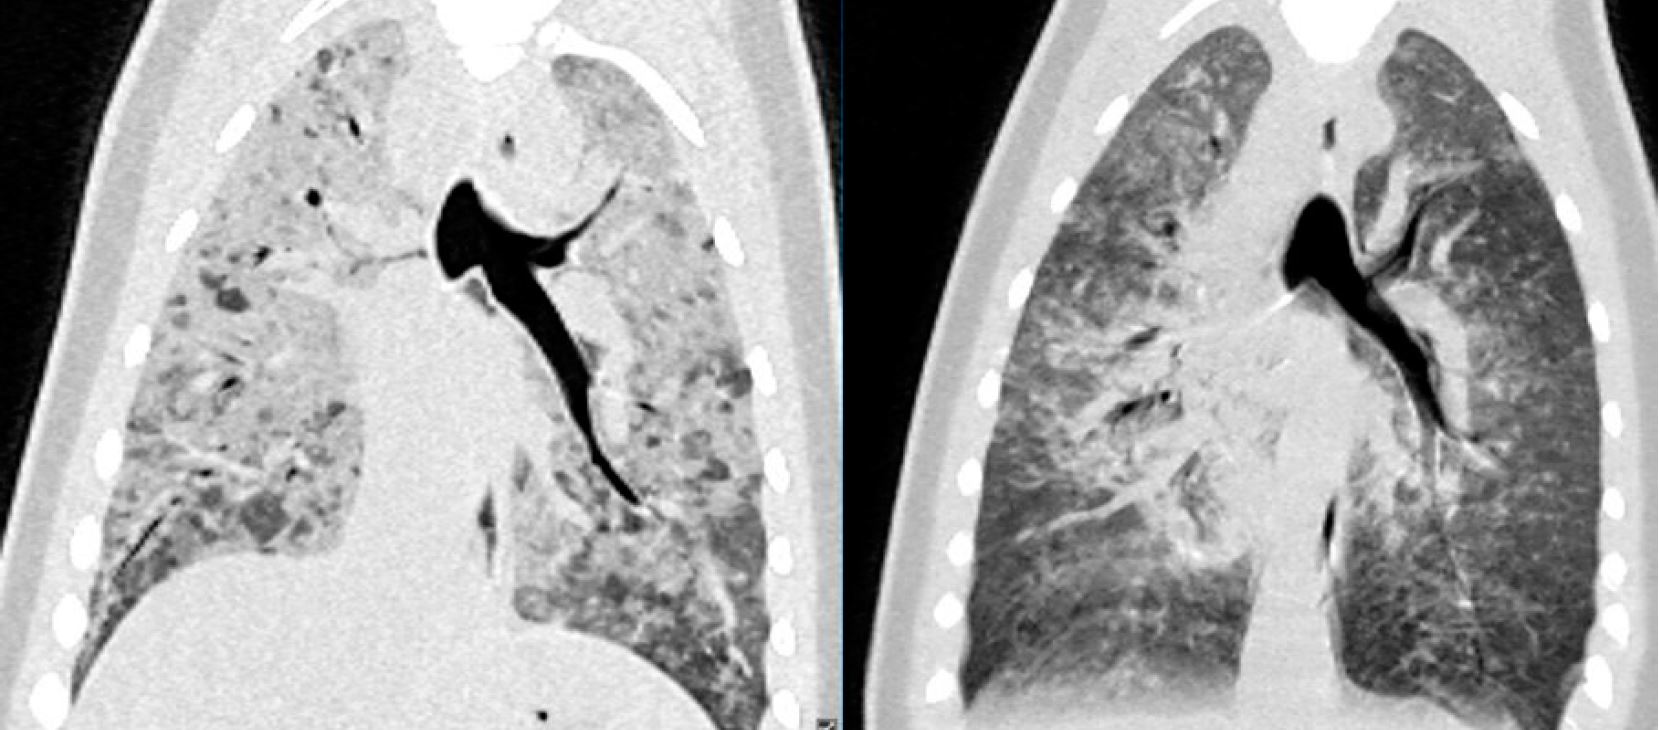

Цікавим виявленням було те, що всі КТ-сканування показали чіткі інтерстиціальні та альвеолярні зміни в легенях (мал. 4). Зверніть увагу на відмінності від сканування нормальних легенів собаки (мал. 5). Швидше за все зміни були викликані ателектазом внаслідок реакції апное, пов’язаної з анестезією. Тюлені були інтубовані та штучно вентильовані, але лише після того, як вони були достатньо анестезовані після внутрішньом’язової ін’єкції. Це могло спричинити пригнічення дихання і, отже, зміни в легенях. Ця гіпотеза підтверджується тим фактом, що зміни частково зникли на другому комп’ютерному скануванні Елвіса, яке було зроблено приблизно через 15 хвилин після першого сканування (мал. 6).

Малюнок 4: Ф ронтальне MPR і аксіальне КТ-зображення у вікні кістки Вінсента показують дифузні інтерстиціальні та альвеолярні інфільтрати. Ці знахідки різною мірою були помічені в усіх трьох тюленях.

Малюнок 5: Фронтальні та аксіальні зображення здорової собаки демонструють нормальний вигляд легеневої паренхіми.

Малюнок 6: Фронтальні зображення грудної клітини Елвіса на одному рівні показують зменшення інтерстиціальних/альвеолярних змін між серіями сканування. Праве сканування було зроблено через 15 хвилин після лівого.